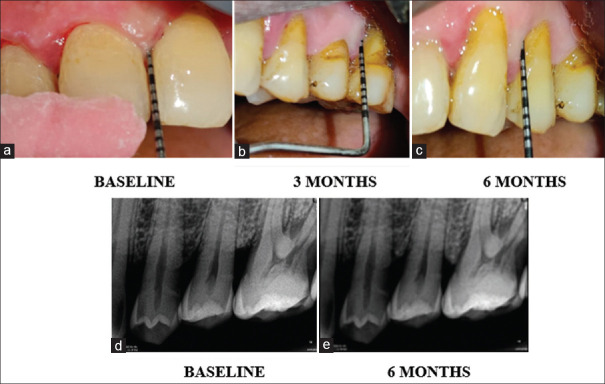

Background and objectives: Many Ayurvedic and herbal medications are used to overcome the drawbacks of allopathic medications. The objective of the current study was to assess and contrast the osteoanabolic effects of Picrorhiza kurroa and F. bengalensis gel on the quantity of bone fill in Stage III periodontitis using Radiovisiography (RVG).

Materials and methods: In the present split-mouth trial, 44 bilateral intrabony defects (IBDs) were randomly assigned to two groups. Group I received nonsurgical periodontal therapy (NSPT) alone, whereas Group II received NSPT along with Picrorhiza Kurroa and Ficus Bengalensis gel. The IBD fill using RVG was the primary outcome measurement and secondary outcomes were probing pocket depth, clinical attachment level, plaque index, and modified sulcus bleeding index reported at baseline, 3 months, and 6 months.

Results: Both the study groups exhibited improvements in the measurements that were evaluated, although Group II significantly outperformed Group I in terms of IBD fill and clinical parameters.

Conclusion: As a supplement to NSPT, the use of picrorhiza kurroa and ficus bengalensis gel is more advantageous in obtaining superior clinical and radiographic outcomes after 3 and 6 months.